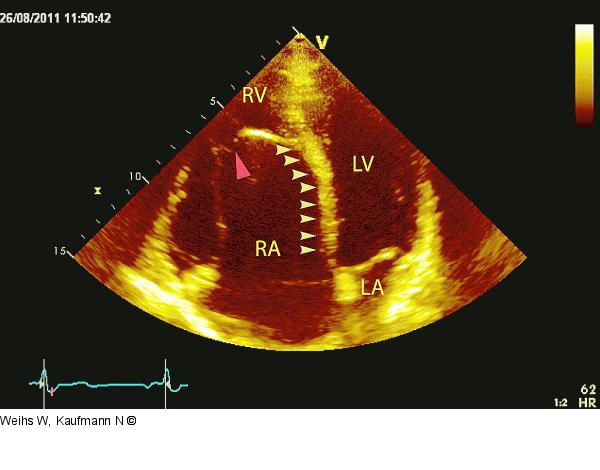

Abbildung 4: Vierkammerblick Apikaler Vierkammerblick. Das septale Trikuspidalsegel ist mit dem Septum verwachsen, dysplastisch und nach apikal verlagert (gelbe Pfeile). Das anteriore Segel ist extrem elongiert und imponiert wie ein Schiffsegel (roter Pfeil). |

Apikaler Vierkammerblick. Das septale Trikuspidalsegel ist mit dem Septum verwachsen, dysplastisch und nach apikal verlagert (gelbe Pfeile). Das anteriore Segel ist extrem elongiert und imponiert wie ein Schiffsegel (roter Pfeil). |